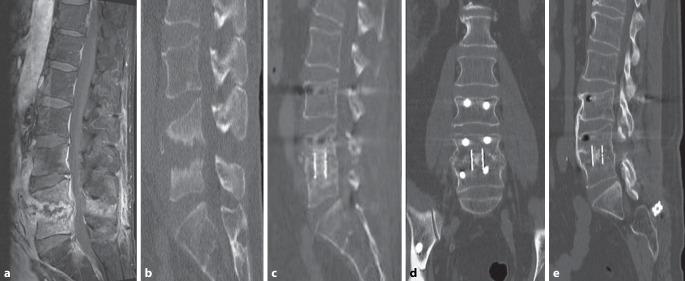

Methods: This retrospective study included 29 patients with pyogenic spondylodiscitis who underwent surgical debridement, interbody fusion, and pedicle screw fixation between February 2018 and March 2023. Patients received PerOssal carriers loaded with either gentamicin (Group A, n = 14) or vancomycin (Group B, n = 15). Clinical outcomes, including fusion rates, infection control, complications, and inflammatory markers, were analyzed.

Results: Baseline characteristics between groups were comparable. Fusion rates at 3-6 months' follow-up were 92.8% (13/14) in Group A and 80.0% (12/15) in Group B, without significant differences (P > 0.05). Both groups showed significant reductions in white blood cell counts and C‑reactive protein levels postoperatively, without inter-group differences (P > 0.05). Complications included cerebrospinal fluid leakage, hematoma, pulmonary embolism, and wound infections, all managed successfully with no recurrent infections observed.

Conclusion: In the short term, PerOssal carriers loaded with either gentamicin or vancomycin demonstrated effective infection control for pyogenic spondylodiscitis and high interbody fusion rates. Moreover, no apparent adverse effects on bone healing were associated with the local administration of high-concentration antibiotics.